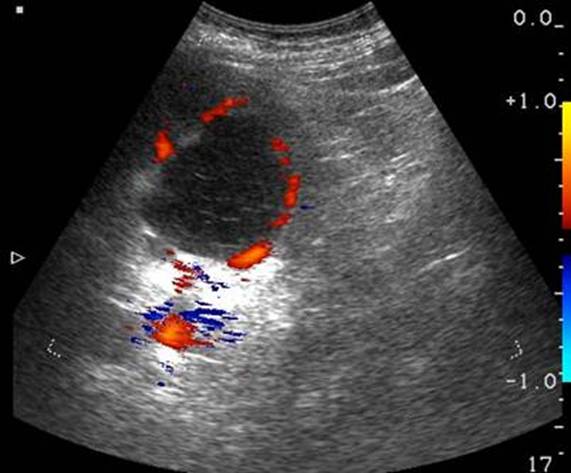

Дані інструментальних

методів

дослідження

(УЗД нирок та

сечових

шляхів, екскреторна

урографія, сканографія, комп’ютерна

томографія)

допомагають

встановленню

діагнозу.

При

рентгенологічному, ультразвуковому

дослідженні

нирок, комп’ютерній

томографії

знаходять

розширення і

деформацію

ниркових

мисок

різного

ступеня

вираженості, асиметрію,

зморщення

нирок.